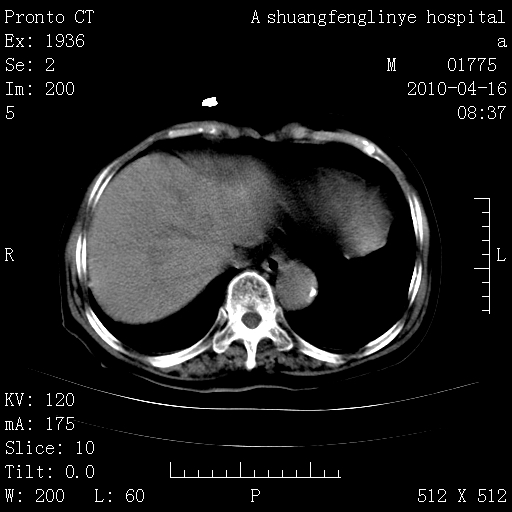

标题: CT25784:咳痰、请会诊!结核? [打印本页]

标题: CT25784:咳痰、请会诊!结核?

陈旧性结核,胃腔扩大,脾脏受压后移

考虑左肺上叶增殖灶、纤维灶。

慢支肺气肿,左上陈旧性结核,主动脉冠脉钙化

典型 夹层动脉瘤。 内膜瓣钙化移位

1)左肺上叶结核(纤维、增殖病灶)。2)冠状动脉及主动脉钙化。

1)左肺上叶结核(纤维、增殖病灶)。2)冠状动脉及主动脉钙化。肺动脉高压